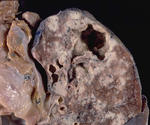

Верифицированный "каверкот"

"Туберкулёз" довольно часто носит маску "злокачественного процесса"

Интересный журнальный случай.

Первоначально эти изменения были расценены, как рак лёгкого.

Последняя иллюстрация - динамика через 14 месяцев.

Кавернозный туберкулёз

Макропрепараты

От Павла Власова